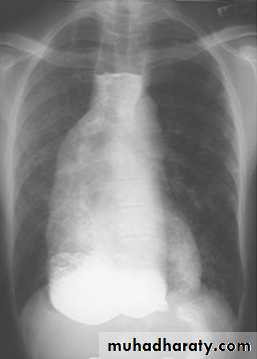

Caput medusae:

Is the appearance of distended and engorged paraumbilical veins, which are seen radiating from the umbilicus across the abdomen.Investigations: